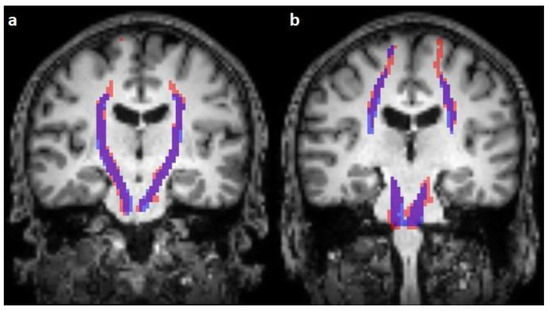

The corticospinal tract traversed the ventral part of the pons in 100/100 cases (100%), traversed the middle-third of the crus cerebri of the mesencephalon in 100/100 cases (100%), traversed the posterior limb of the internal capsule in 100/100 cases (100%), and originated from the medial part of the precentral gyrus in 89/100 cases (89%) (Figure 1, Figure 2 and Figure 3).

Figure 2.

Comparison of the predicted (blue) and reconstructed (red) course of the corticospinal tract on coronal T1-weighted images (a,b).